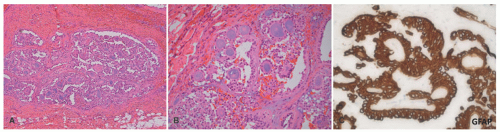

FIGURE 24-5. A-C, Neurofibroma from the scalp of an 11-year-old female with NF1. A, Plexiform profile is surrounded in part by diffuse neurofibroma. B, Serpentine architecture is displayed in these foci with a pure plexiform pattern. C, Mild degree of scattered nuclear enlargement and hyperchromatism without apparent sarcomatous overgrowth should not be a source of concern in most cases.

A contrasting histologic pattern of dermal and subcutaneous involvement is present in the NF1-associated NF where the tumor has a diffuse and/or plexiform appearance with growth through the dermis and replacement by bland spindle cells in a pale-staining eosinophilic stroma (Figure 24-4A-C). Adnexal structures in the dermis are surrounded, but not displaced, by the proliferation. The plexiform profiles may be present as one or more bundles of spindle cells within the background of diffuse NF or as separate distinct profiles in the dermis and/or subcutis (Figure 24-4A-C). Within the dermis, the short to fusiform spindle cells have elongated, bland nuclei; nuclear enlargement with hyperchromatism is uncommon in the dermalbased NFs, but may be seen in the deep soft tissue NFs in older children and young adults.20 When the subcutis is involved as it often is, the growth is usually contiguous with a dermal component and the fat is overgrown in a manner similar to dermatofibrosarcoma protuberans (DFSP) and some of the fibrous tumors of childhood (Figure 24-4A-C). The plexiform pattern of NF is characterized by multiple circumscribed bundles of pale-staining spindle cells in a myxoid background (Figure 24-5A-C). The contours of the plexiform bundles are sharply demarcated as distinct profiles in the deep dermis and subcutis. Nuclear enlargement and atypia are uncommon in the more superficial plexiform NFs but, if present, should not be viewed as indicative of sarcomatous transformation (Figures 24-5C and 24-6).